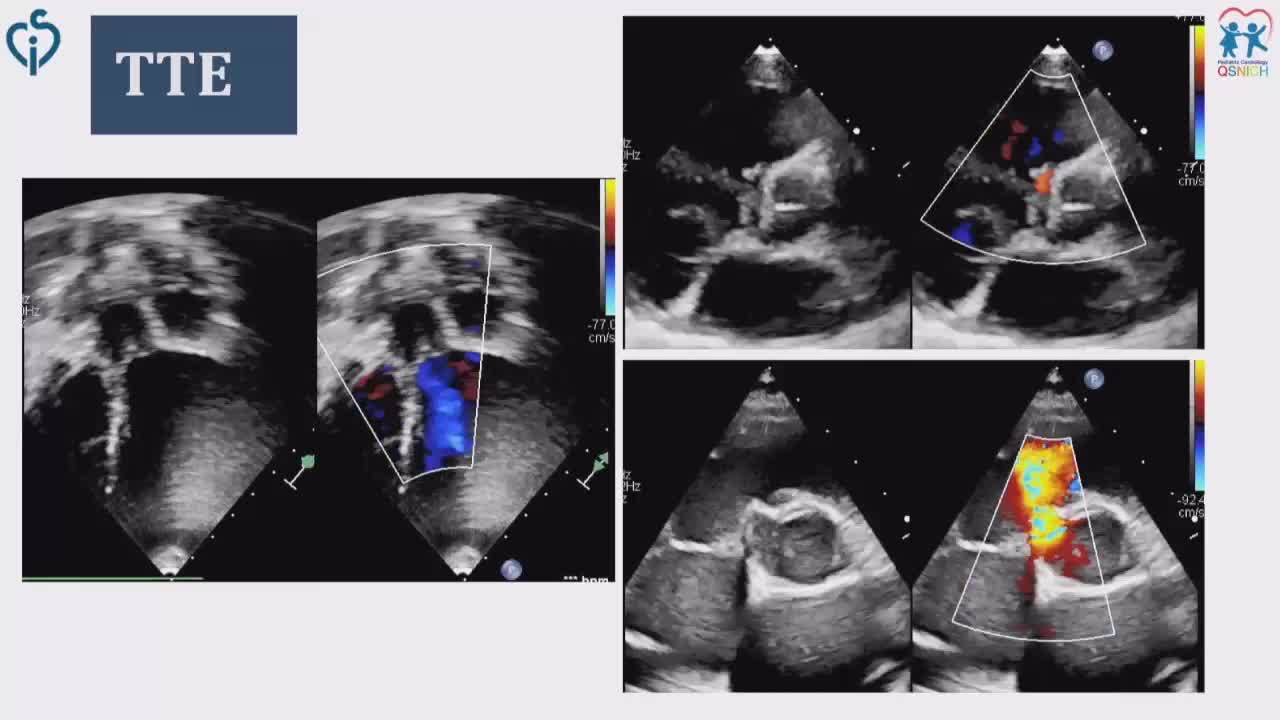

CSI CATHLAB LIVE - VSD CLOSURE WITH THE NEW OCCLUTECH PMVSD OCCLUDER (ANTEGRADE APPROACH)